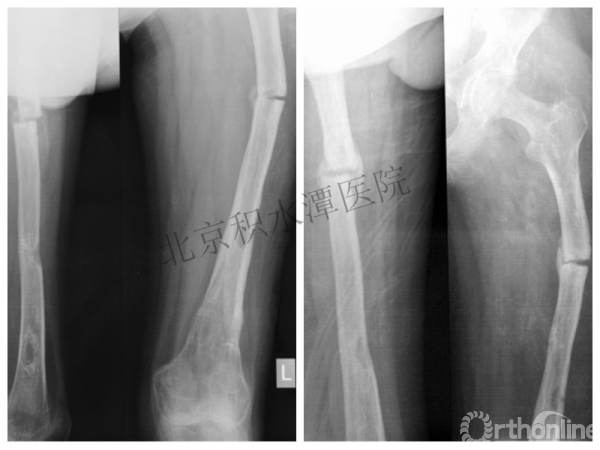

病例分享三

男孩、9岁,滑雪受伤,胫腓骨螺旋形骨折(粉碎性)

这个病例郭教授在积水潭医院骨科高研班时多次讲到,也在互动交流中惊人地看到,了解到现实之令人难以想象!

手法整复,石膏制动!

整复后7天

儿童具备强大的愈合潜力,同样也有极强的塑形能力

某种情况下,The best treatment is no treatment! 最佳治疗反而是不治疗!因为很多骨折依靠儿童强大的塑形能力和特点完全可以得到满意的结果!

病例分享四

女孩、8岁,桡骨远端骨折

原始损伤

伤后1个月

伤后14个月

病例分享五

女孩、6岁,股骨干骨折

牵引后4周

伤后18月

没有任何外观和功能障碍!相信每位小儿骨科医生都会有很多类似的病例!除非您不承认或者没有认识到塑形!